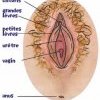

Nuit de noces en Algťrie : Petites blessures, profondes sťquelles

En Algťrie, pour nombreuses femmes, le souvenir de la nuit de noces est celui d’une douleur intense, d’une dťchirure physique, et (...)

Gr‚ce ŗ ma bartholinite…

ę Madame, vous souffrez d’une Bartholinite. C’est une pathologie assez grave si elle est nťgligťe. Vous avez bien fait de consulter (...)